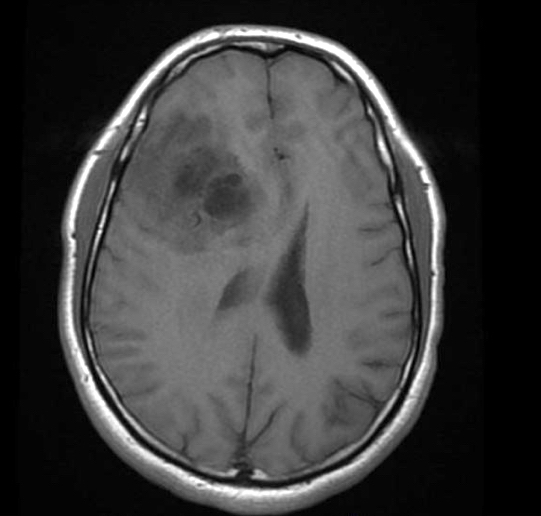

Radiology description

- Computed topography (CT):

- Mixed density (hypodense and isodense) located in cortex or subcortical white matter (Radiology 2017;284:316)

- High attenuation areas, likely from calcifications

- MRI:

- Heterogeneous on T1 and T2 weighted imaging

- Typically no diffusion restriction

- Poorly circumscribed borders (AJNR Am J Neuroradiol 2017;38:678)

- Cystic changes are relatively common (Radiology 2017;284:316)

- Contrast enhancement present in < 20% of WHO grade 2 tumors and > 70% of WHO grade 3 tumors (AJNR Am J Neuroradiol 2012;33:852, Eur J Cancer 2019;107:15)

- Elevated 2HG by magnetic resonance spectroscopy could serve as radiologic surrogate of IDH mutation status (Nat Med 2012;18:624)

Radiology images